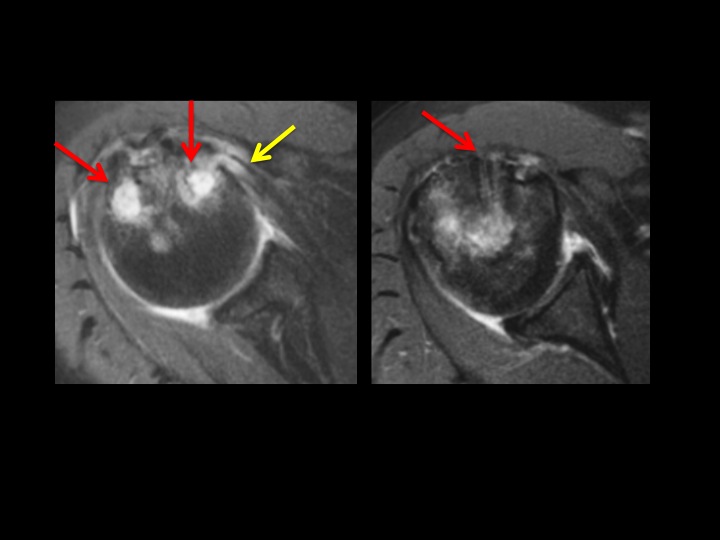

67 yr old female 1 year post RCR with shoulder pain + instability

This is always a source of confusion. There are 4 bioabsorbable anchors: 3 entering anterior to posterior at the supraspinatus insertion, 1 related to biceps tenodesis. There is a wide zone of Dark T1/Bright T2 signal with bone resorption surrounding the cuff fixations screw, but not the biceps tenodesis screw (red arrows). The supraspinatus tendon is thick and frayed, but intact. There is partial tearing of the infraspinatus and a small intrasubstance tear at the subscap insertion (yellow arrows). To what extent is the lysis surrounding these screws abnormal (there is some normal degree of lysis as the screws resorb, extrapolating from tunnel widening with ACL graft fixation). Would you report this? What would you say?